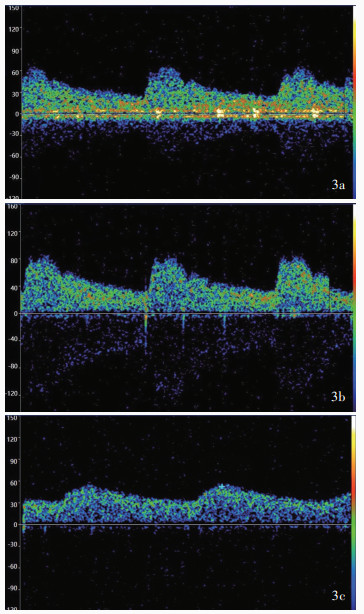

Cheng P , Liu BL , Zhao BB , Yu DL . The utilization of carotid artery ultrasound in diagnosis of internal carotid artery absence and its imaging features. Zhongguo Xian Dai Shen Jing Ji Bing Za Zhi, 2023, 23: 933- 939.

doi: 10.3969/j.issn.1672-6731.2023.10.011

程盼, 刘保龙, 赵碧波, 于德林. 颈内动脉缺如超声诊断要点及其他影像学特点分析. 中国现代神经疾病杂志, 2023, 23: 933- 939.